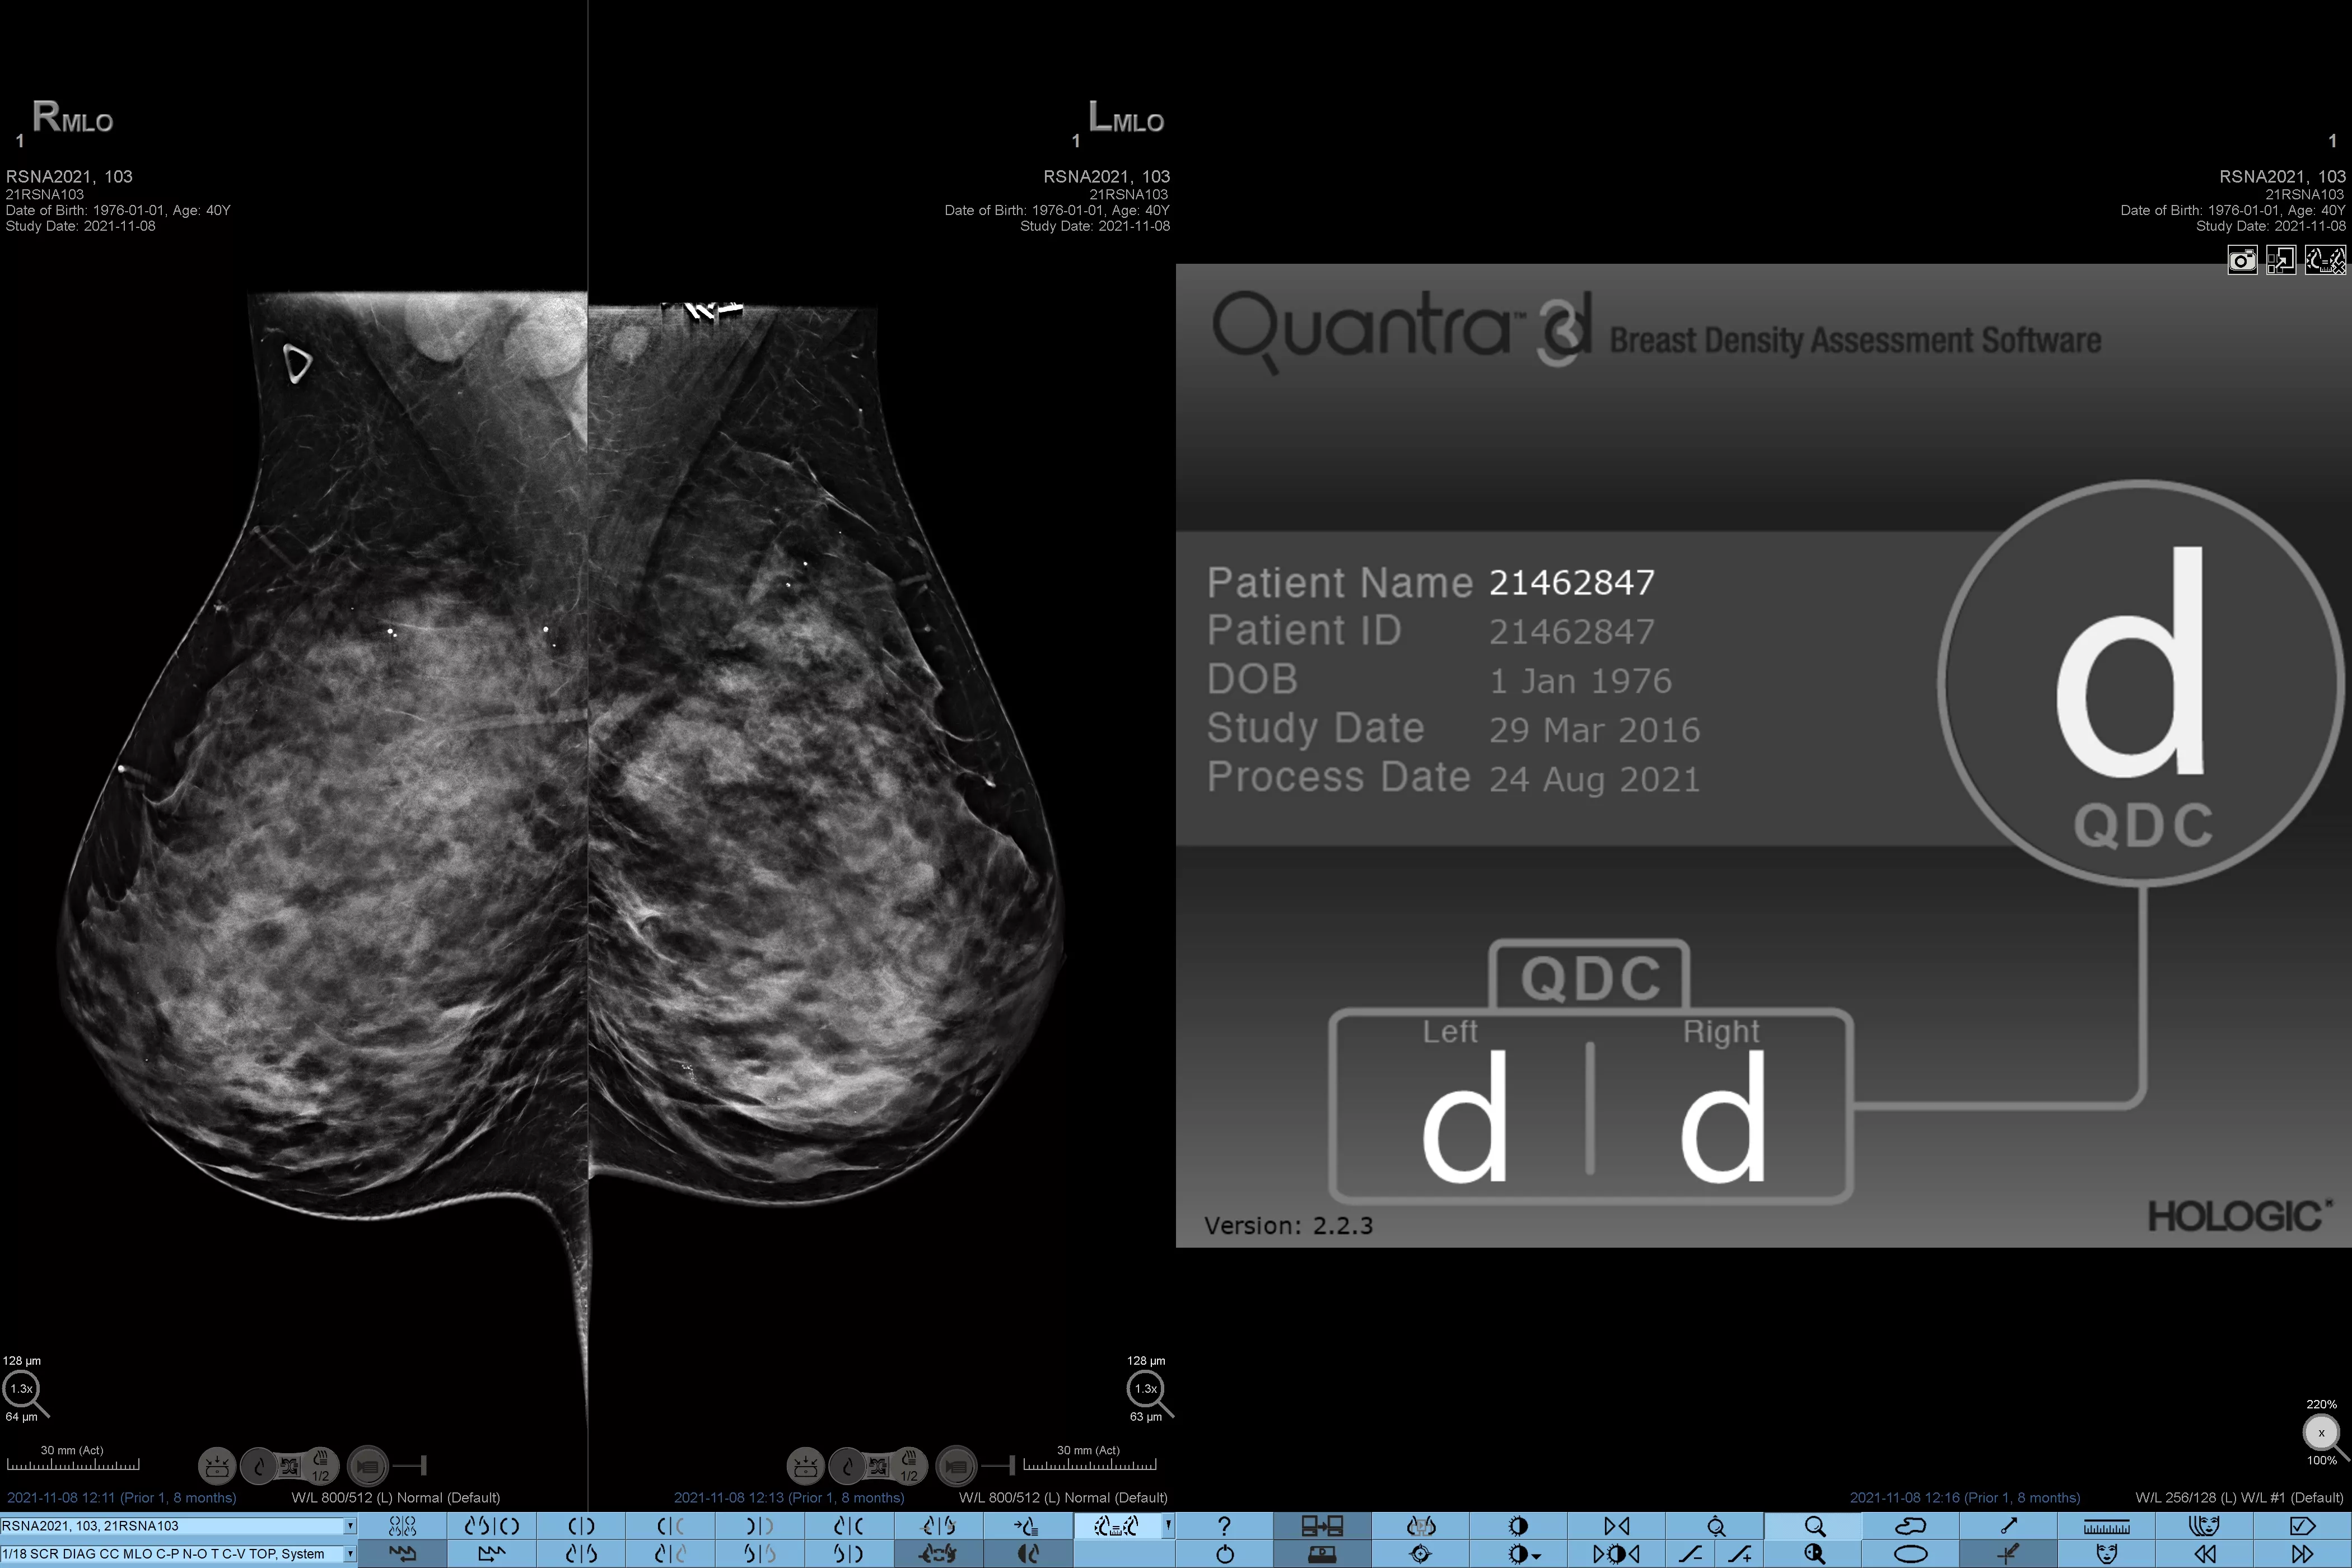

Higher breast density is known to increase a woman’s risk for breast cancer.1 The need for accurate, unbiased analysis is therefore critical. Powered by machine learning, Quantra technology software analyses both 2D™ and tomosynthesis images for distribution and texture of parenchymal tissue. It categorises breasts in four breast composition categories consistent with guidance from the American College of Radiology (ACR) BI-RADS Atlas 5th Edition.2

Objective machine learning algorithm that assigns breast density category based on analysis of breast tissue texture and patterns.

Standardisation

Standardise reporting across the radiology practice and provide a high standard of care.

Quantra software’s unbiased algorithm analyse both 2D and tomosynthesis images to support your analysis by:

• Overcoming subjectivity in visual assessment, providing more consistent, and more reliable scoring.*

*Scores are based on ACR BI-RADS categories, in line with the revised guidance by the American College of Radiation (ACR) BI-RADS Atlas 5th Edition. This accounts for pattern and texture, compared with volume, when determining density.

8. Breast composition categories as described in ACR BI-RADS Atlas.